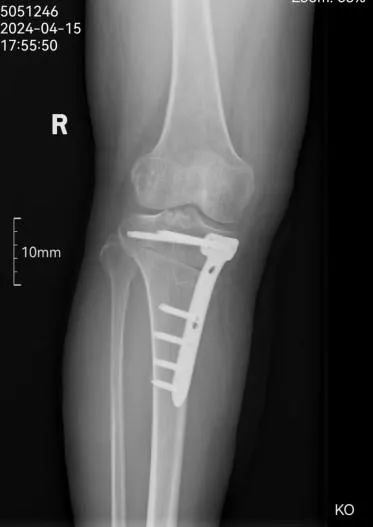

45岁的患者牛某,因5年前外伤致右胫骨平台骨折,未行手术治疗,伤后半年开始负重行走,致使右膝关节不稳定,且逐年加重。患者因右膝关节不稳定,不敢快速行走及下台阶,且摔倒数次,产生了恐惧心理。辗转多家医院后,均疗效不明显。 听闻“京长合作”首都医科大学附属北京积水潭医院每月定期派专家来长治二院骨科坐诊、查房、手术的医讯,主动要求北京积水潭专家手术治疗,近日来我院就诊要求住院手术治疗。 门诊经查体及阅读各项检查后以“右胫骨平台骨折畸形愈合”便收住院。 入院诊断: 1.右胫骨平台骨折畸形愈合 2.高血压病 住院期间,北京积水潭医院骨科吴宏华副主任医师结合查体及辅助检查,考虑患者畸形为关节外畸形,下肢力线向前内侧偏移,建议行胫骨内侧高位双平面截骨纠正对位及力线。考虑开放行双平面截骨,创伤较大,建议3D打印HTO截骨导板,在导报引导下行微创双平面截骨。在全身麻醉下在截骨导板引导下行截骨矫形术。 术后3天患者牛某持助行器下地行走,右膝关节不稳定感觉消失,恐惧心理消失,心情舒畅,对手术效果非常满意。 此次手术是在北京积水潭吴宏华副主任医师指导下,长治二院首次将HTO截骨技术应用于创伤骨科,是“京长合作”带给长治二院骨科发展的新动力,更为我市骨病患者带来的福音。 科室推荐 创伤骨科二病区隶属于长治二院骨科创伤专业,成立于 1978年建院之初,至今已历时 40 余年。创伤二病区现有开放床位 35 张,共有医师 10名(含返聘医师),护士 9 名。其中主任医师 1名,副主任医师 1 名、主治医师 6名、住院医师 2 名。 病区主任:李黎明,主任医师、长治市工伤医疗鉴定专家、北医三院进修学员,擅长复杂骨折的手术修复,尤其在骨盆骨折、关节周围骨折的手术治疗方面技术精湛。 创伤二病区诊疗疾病范围:肩胛骨骨折、肩(胸)锁关节脱位、锁骨骨折、肱骨近段骨折、肱骨干骨折、肱骨髁骨折、尺骨鹰嘴(冠突)骨折、尺桡骨骨折、桡骨远端骨折、各类型骨盆骨折、髋臼骨折、股骨头骨折、股骨颈骨折、股骨粗隆间骨折、股骨干骨折、股骨髁骨折、髌骨骨折、胫骨平台骨折、胫腓骨骨折、各类型踝关节骨折(韧带损伤)、各类型开放(闭合)性软组织损伤、陈旧性骨折不愈合、骨感染(骨髓炎)、内固定周围骨折、骨折非手术治疗、骨折康复指导等。 咨询热线 0355—3126025 主任医师 创伤骨科二病区主任 擅长复杂四肢骨折、骨盆骨折,脊柱骨折、颈椎病、腰椎管狭窄等的诊治。在肢体复杂损伤、脊柱退变疾病方面有较多深入研究。多次在北京、太原等省内外三甲医院进修学习,具有丰富的理论知识。 【学术任职】 长治医学院副教授、长治市骨科专业委员会委员、长治市足踝外科委员会委员、长治市医疗专家库成员,长治市工伤、司法鉴定专家组成员。在国家级省级专业杂志发表论文学术论文10余篇,在专业学术领域积累了丰富的临床经验。 医生推荐 徐彦芳 副主任医师 骨科学硕士 北京大学国内访问学者 【专业特长】 【学术任职】 咨询热线 李黎明主任 13097569000 徐彦芳医生 15635598825 供 稿丨徐彦芳 编 辑丨卞 晨 审 核丨雷 赫